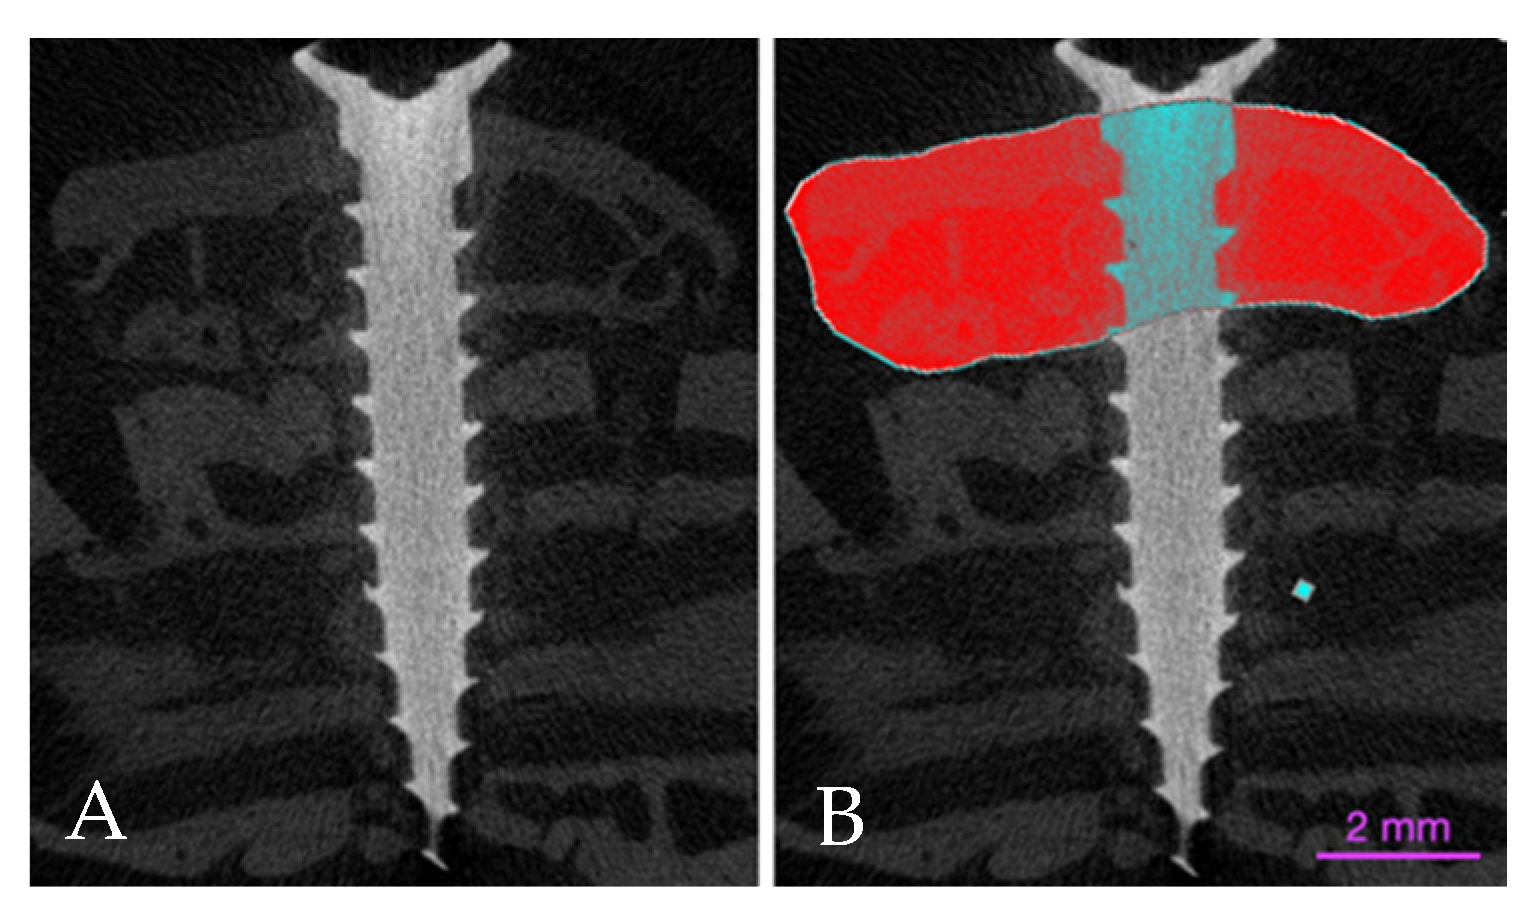

2.6. Micro-CT Evaluations

3.2. Micro-CT Evaluation